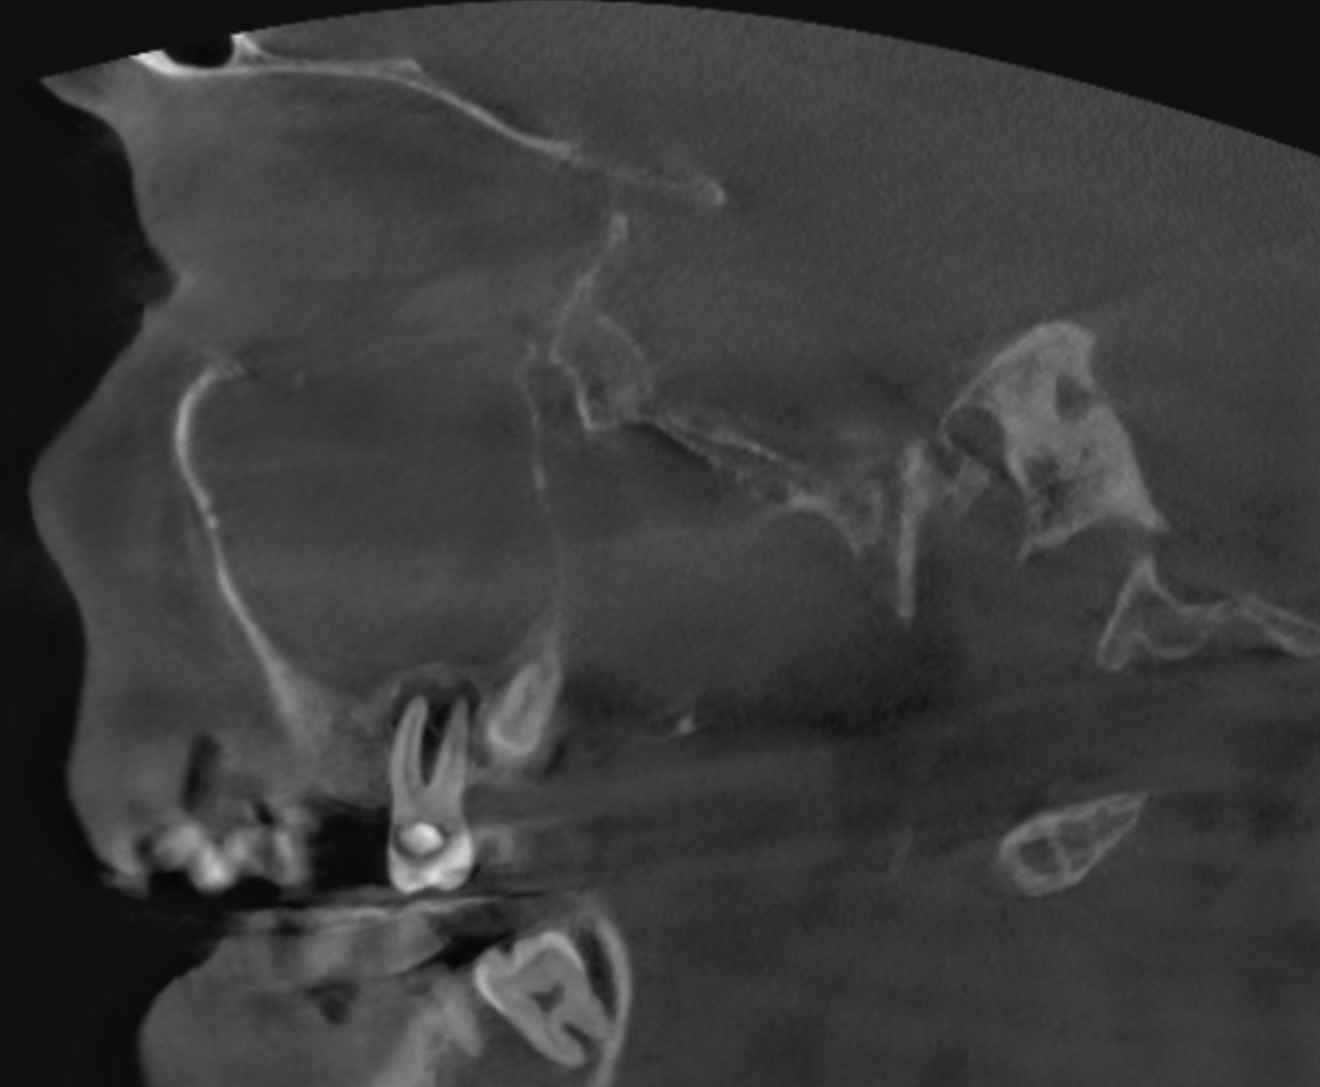

Figs. 1a & b: Initial small-volume CBCT scan, panoramic view (a) and cross-section of tooth #17 (b).

The 61-year-old male patient wanted to have his missing maxillary right teeth replaced with implants. After examination by an implantologist, he was referred to our dental office for further dental treatment because of the findings of a small-volume CBCT scan taken: advanced inflammation and bone loss were visible in the periodontal tissue of the maxillary right second molar and severe maxillary sinusitis was observed (Figs. 1a & b).

The extent of the inflammation was shocking (Figs. 2a & b). Not only the maxillary sinus (Fig. 3) but the ethmoid and sphenoid sinuses too were involved, and the inflammation had spread towards the right cavernous sinus as well (Fig. 4). At this point, extraction may have been the first choice for most dental clinicians, but we had to keep in mind that invasive treatment may have increased the risk of cavernous sinus thrombosis, a potentially avoidable possibility. There are very few circumstances under which a dental procedure can cause very severe or even lethal consequences, but this case approached such a situation.

Fig. 2a: Large-volume CBCT scan, sagittal cross-section of the buccal roots.

Fig. 2b: Large-volume CBCT scan, sagittal cross-section of the palatal root.